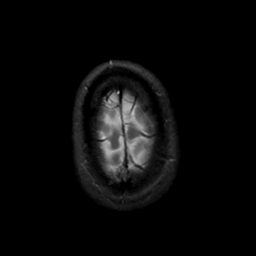

MR Study #22, December 1, 1991 -- Slice #46

[Home][Help][Clinical][Tour 1][Tour 2] Slice 46